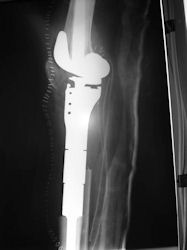

Examples of radical limb sparing surgeries for osteosarcomas in various anatomic locations (distal femur, proximal tibia, proximal humerus, scapula)

In each case, the tumor and bone from which it arose were resected. This required meticulous dissection, mobilization and preservation of adjacent pertinent neurovascular structures. In each case presented here, the defect was reconstructed with a special modular segmental tumor prosthesis. This also replaces the adjacent joint in many instances.

| Proximal Tibia Osteosarcoma: Limb-Sparing Surgery |

Postoperative X-Rays